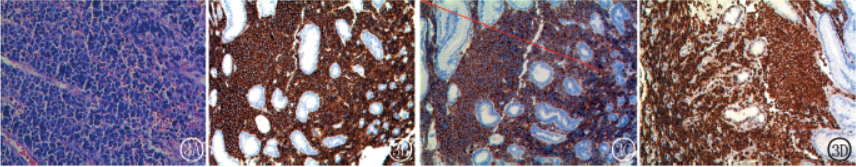

并活检,病理结果(图3)示:NHL(非霍奇金淋巴瘤

),考虑Burkitt淋巴瘤或弥漫大B细胞淋巴瘤

。免疫组化:LCA+、CD20+、CD79a+、CD10+、BCL-6+/-、CD99-、CD2-、CD5-、CD3-、CyclinD1-、TdT-、CD1a-、CKpan-、EMA-、CD56-、S-100-、P53-/+、MP0-、Ki67阳性指数大于95%。

图3病理及免疫组化图(×200)图3AHE染色。图3BCD20+。图3CCD10+。图3DKi67阳性指数大于95%